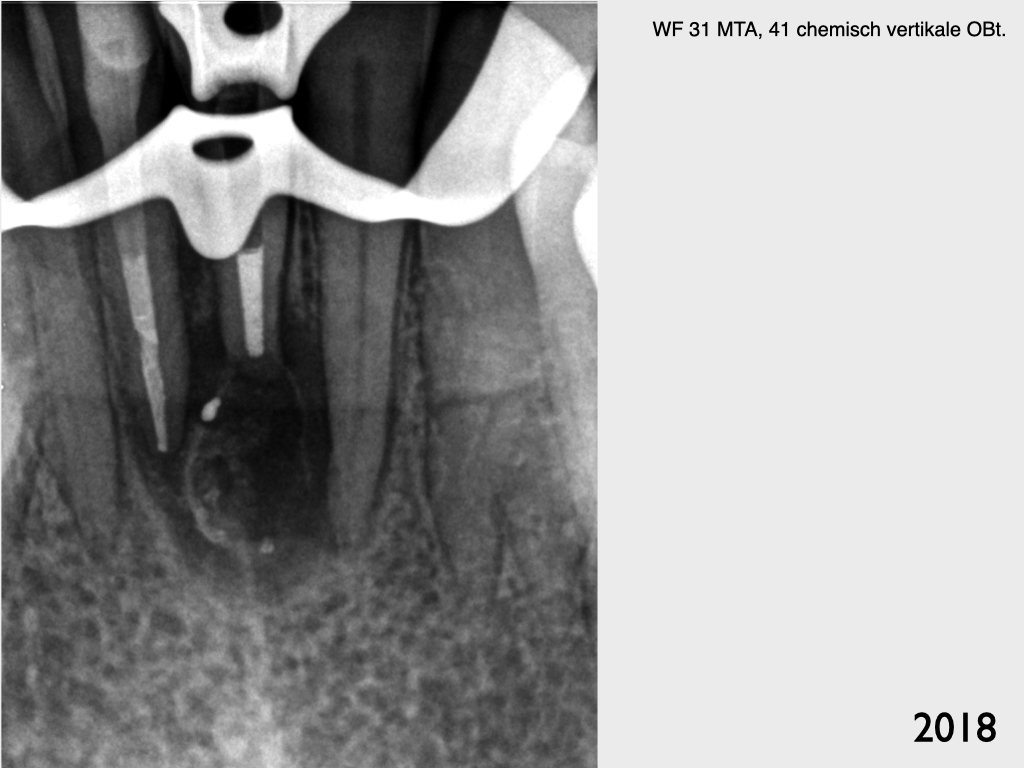

Und wieder ein UK Frontzahn